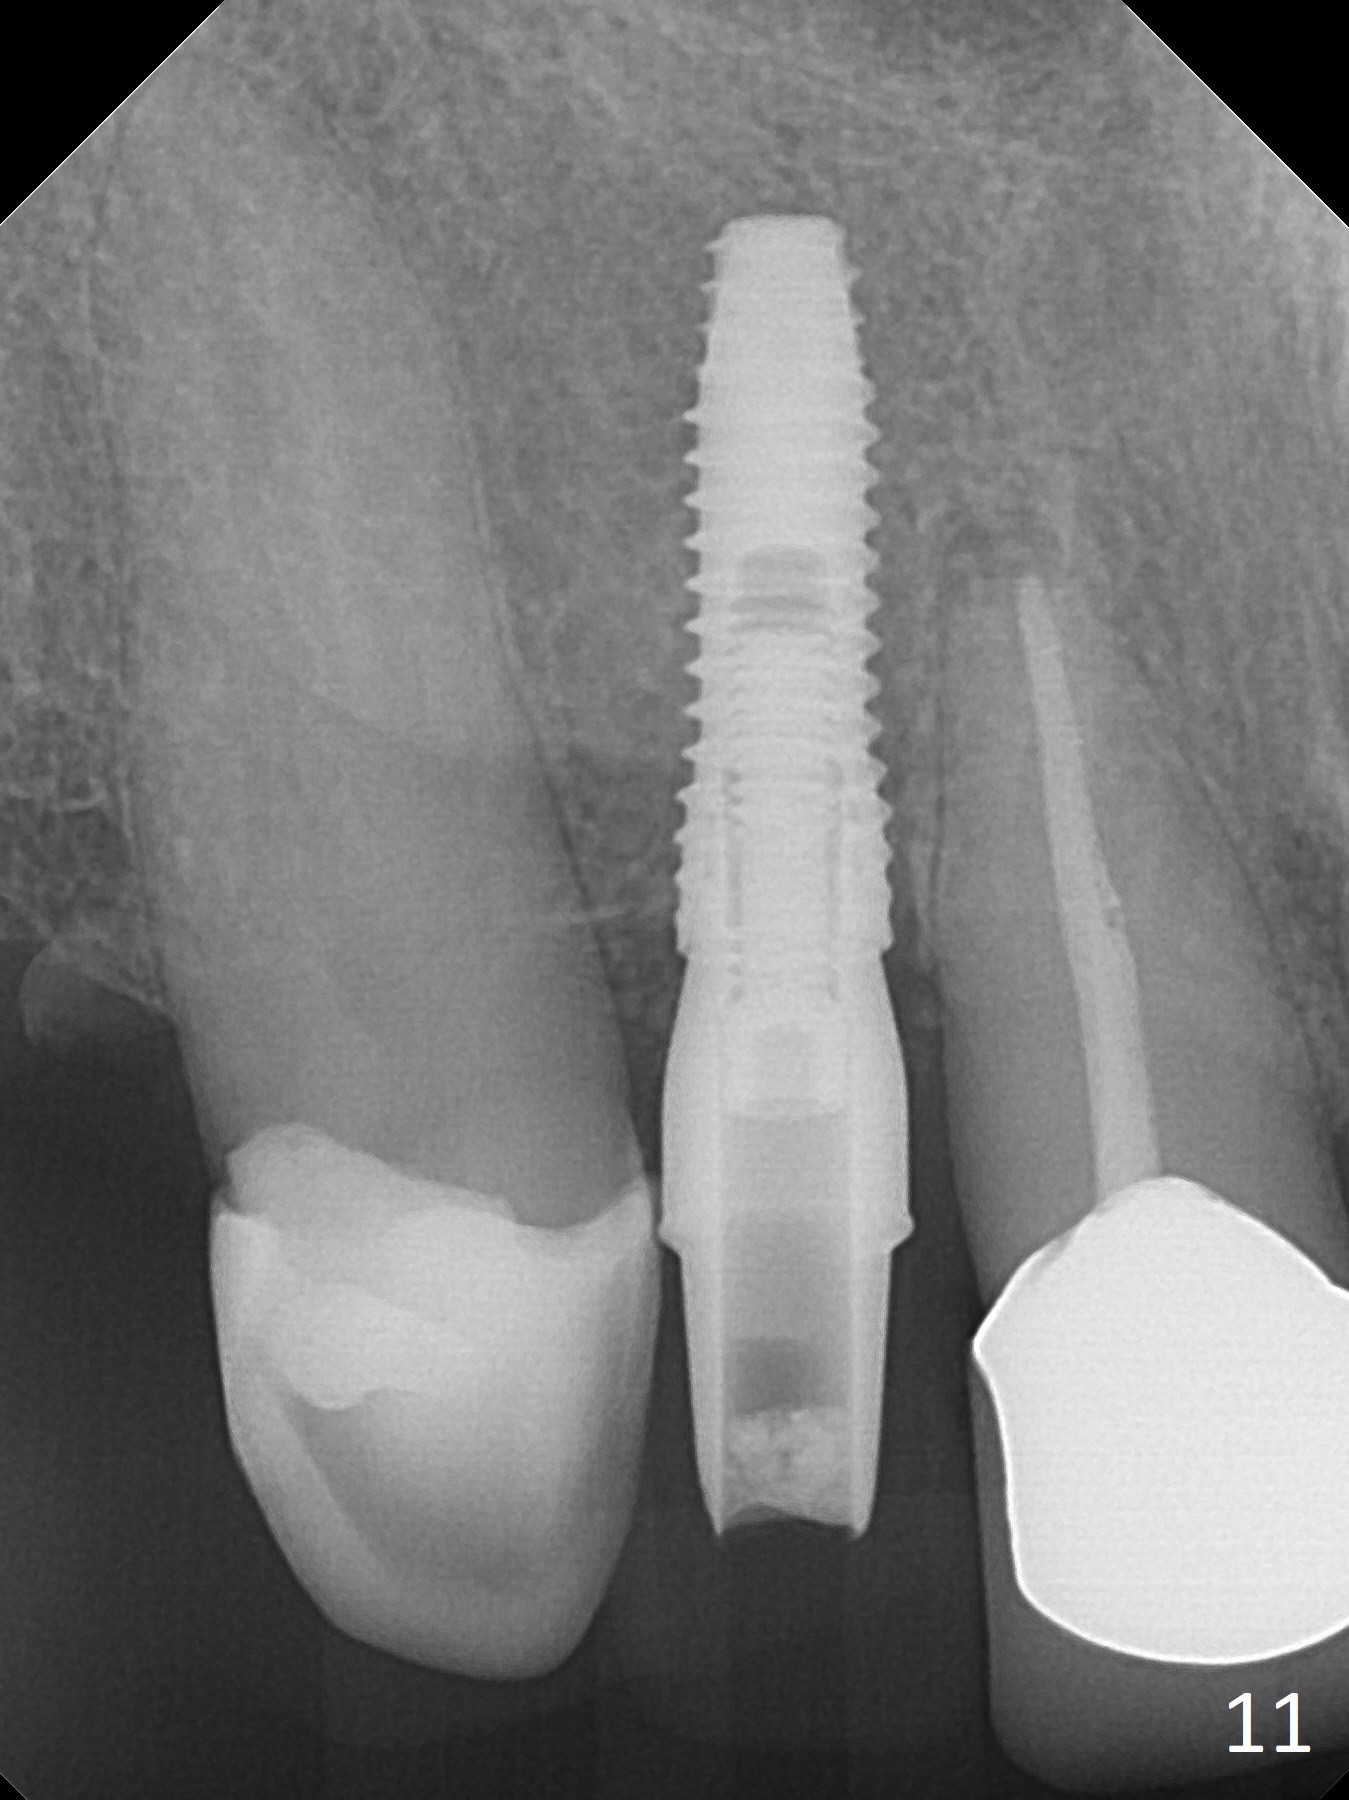

The residual root at #7 is fairly well exposed with buccal gingival recession (Fig.1). The implant placement is flapless (Fig.2-7). What is not shown is that the 3.8x13 mm implant is buccally subcrestally placed (Fig.3). After 1st round of bone graft buccal to the implant, a 4.5x5(5) mm abutment is immediately placed and prepared (Fig.4,5). An immediate provisional is placed after 2nd round of bone graft subgingivally buccally (Fig.6,7). Note the bulging gingiva (*), as compared to that in Fig.4,5. The long implant is chosen because of anterior deep bite (Fig.4) and lack of posterior support (Fig.7).

The gingiva adapts well to the provisional 1 week postop (Fig.8). The buccal gingiva remains recessive and the buccal plate is concave 5.5 months postop (Fig.9-11). It appears that the coronal portion of the buccal plate is resorbed 12 months postop (6 months post cementation, Fig.12 >). Socket shield or smaller diameter implant should have been done to avoid bone loss. Reanalysis of CBCT reveals that implantation apparently increases the bone width and that the buccal plate resorption is not so severe (Fig.13,14 (>: coronal end of the buccal plate)). Panoramic X-ray is taken 2 year 5 month post cementation.